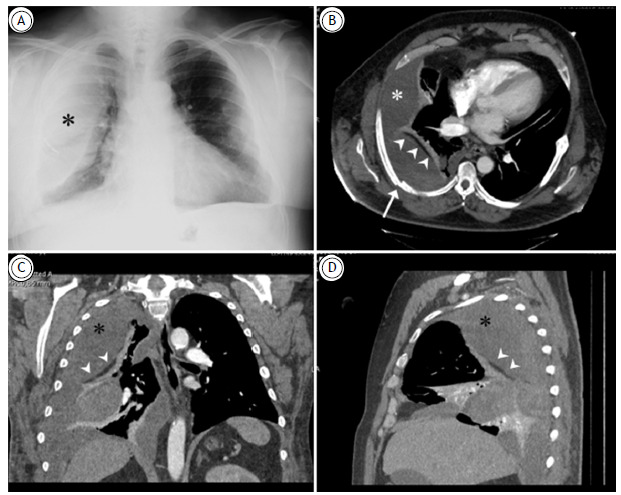

右胸膜外血肿,胸部外伤所致。胸膜外脂肪征。

Right extrapleural hematoma due to thoracic trauma. The extrapleural fat sign.